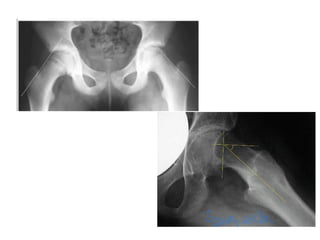

DDH

SCFE

Congenital coxa vara

Hilgenreiner’s epiphyseal angle